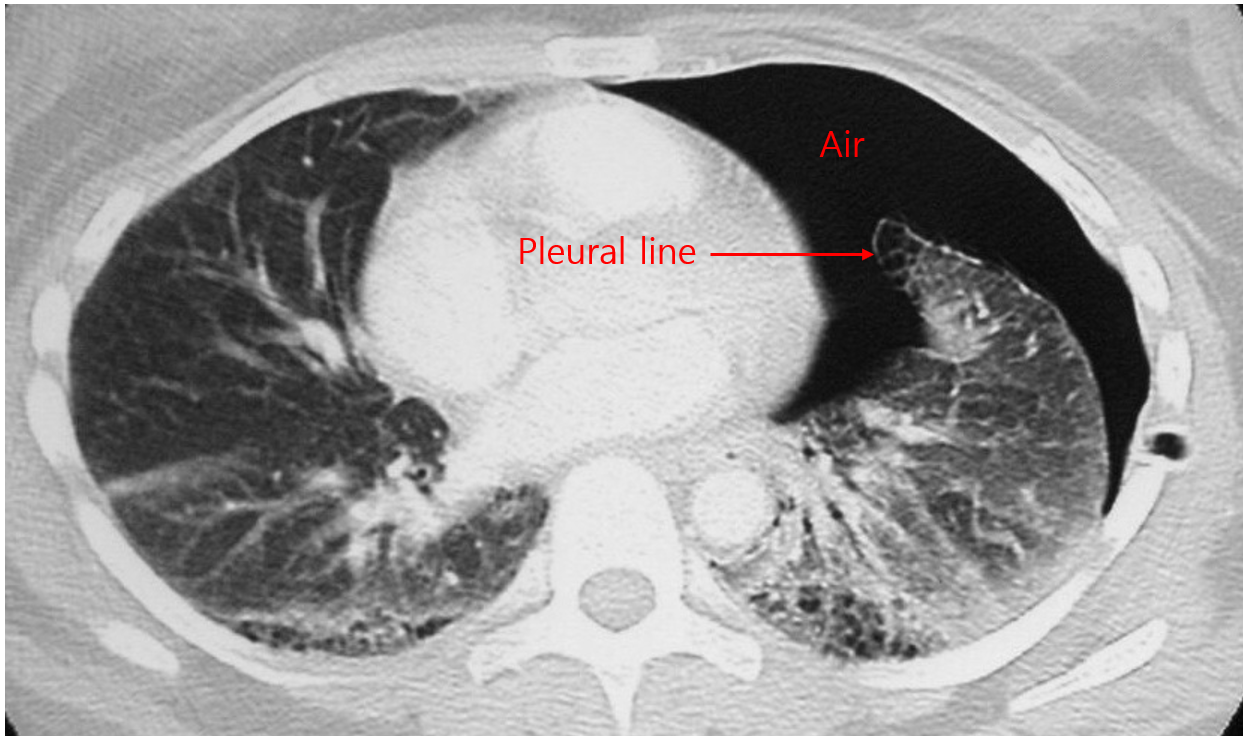

4) 검사소견: CXR

(1) 얇은 pleural line이 보임: Visceral pleura가 보이는 것

기흉의 부피가 커서 폐가 collapse된 경우 line의 형태로 보이지 않을 수 있음

(2) Pleural line 바깥쪽으로 vascular marking의 소실

* 단순히 pleural line이 보이는 것뿐만 아니라, pleural line이 흉강을 따라 끊어지지 않고 tracing이 가능해야 하며 vascular making의 소실이 동반되어야 기흉으로 진단할 수 있다. 피부가 접혀있는 흔적(skin fold), scapula 등이 pleural line으로 오인될 수 있기 때문이다.

(1) CT: CXR 해석이 어려울 때, 동반 폐질환 감별이 필요할 때